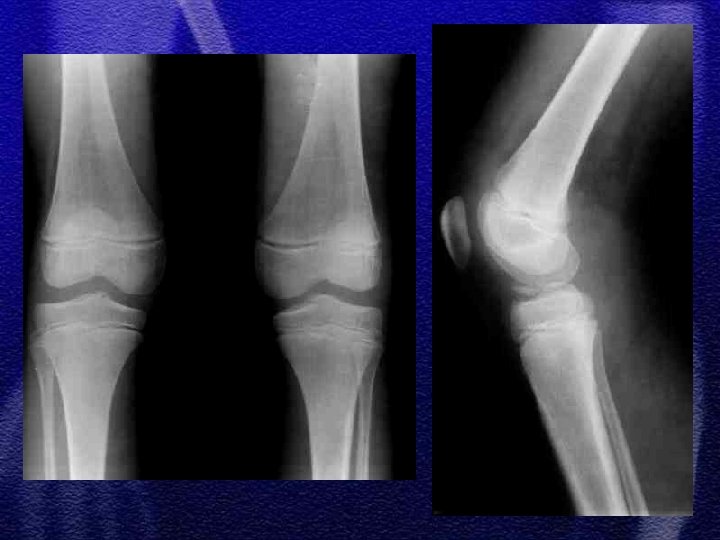

§ Następuje w wyniku działania dużej siły § Najczęściej typ II wg Saltera-Harrisa § Rzadko typ I bez przemieszczenia oraz typ IV prowadzący do zaburzenia wzrostu kości udowej § W znacznych przemieszczeniach należy ocenić stan krążenia i unerwienia kończyny § Leczenie – nastawienie w znieczuleniu ogólnym, złuszczenia niestabilne można ustalić przy pomocy dwóch skrzyżowanych drutów Kirschnera

§ Oderwanie wyniosłości międzykłykciowej, leczenie - I i II stopień wg Meyersa i Mc. Keevera punkcja leczenie zachowawcze, gips do 6 tygodni w zależności od wieku § Przemieszczenia III° leczenie operacyjne: szew, pętla druciana, zespolenie śrubą przy użyciu artroskopu

§ Występuje bardzo rzadko § Bez przemieszczenia leczy się zachowawczo § Typ i wg Watson-Jonesa operacyjnie - śruba drut Kirschnera

§ Złuszczenia nasady bliższej wyjątkowo rzadkie, obarczone powikłaniem pod postacią zaburzenia wzrostu kończyny co może prowadzić do znacznych odchyleń osi § Złamania bliższej przynasady mogą powodować podobne powikłania